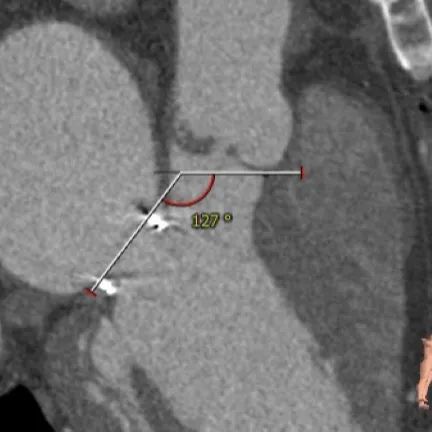

优选右股入路,二尖瓣与主动脉瓣角度:127°。

患者为三叶瓣,主动脉瓣关闭不全,既往有二尖瓣生物瓣置换手术史,主动脉根部与二尖瓣夹角为127°,角度上不影响TAVR手术(大于120°较佳,小于100°有风险);法式窦及STJ结构尚可,升主动脉未见增宽,心脏角度尚可,左室大小明显增大。